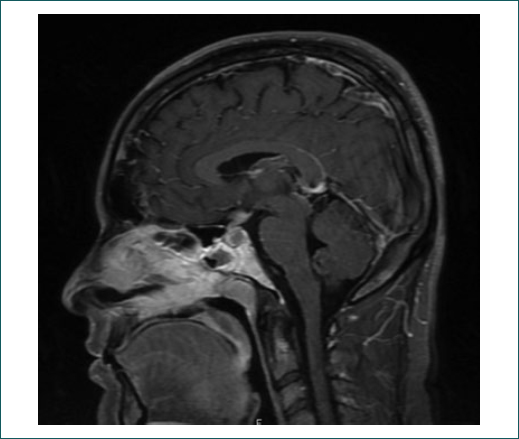

Varón de 31 años con sensación de obstrucción nasal de 3 meses de evolución, con diagnóstico de sinusitis, sin mejoría con tratamiento sintomático. Al cuadro se agregó cefalea intensa, fiebre y diplopía ocasionada por paresia de nervios craneales (NC) III, IV y VI derechos. Las imágenes de tomografía computada (TC) y resonancia magnética (RM) de cráneo presentaron hiperintensidad hipofisaria, así como sinusitis esfenoidal (Fig. 1).

Ante la fiebre persistente, la mononeuropatía craneal múltiple y la pleocitosis con predominio de mononucleares se sospechó tuberculosis en el SNC y se inició tratamiento antifímico, el cual fue suspendido en días posteriores por presentar datos de hepatotoxicidad. El paciente progresó con anemia grave (hemoglobina: 7.6 g/dl) y neutropenia (448 103/mm3), por lo que requirió la administración de factor estimulante de granulocitos/monocitos y de hemotransfusión. Persistió febril, agregándose parálisis del VII NC derecho. La nueva RM de cráneo evidenció realce con engrosamiento dural y sinusitis etmoesfenoidal. Por la pancitopenia y la elevación de la deshidrogenasa láctica, se realizó biopsia de médula ósea que reportó mielodisplasia. El paciente refería persistencia de la obstrucción nasal y aparición de una úlcera en el paladar blando, de la cual se tomó biopsia que reportó inflamación histiocítica perivascular. El rastreo gammagráfico con Ga67 mostró captación en los senos etmoidales (Fig. 2).